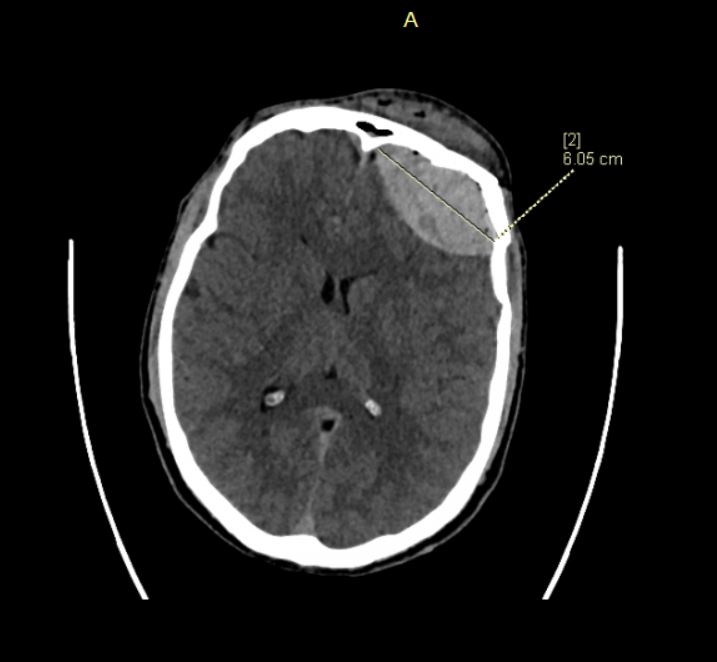

The increasing popularity of electric scooters in Poland is associated with the growing number of e-scooter-related accidents, which often involve head traumas. Although the most common types of injuries are abrasions and cuts to the skin, they sometimes include severe brain injuries. Most e-scooter accidents occur in the warm months. In winter, when there are unfavorable conditions for using this means of transport, e-scooter-related accidents are rare. Described in the text are 2 cases of severe cases of skull and brain injuries which required neurosurgical intervention. In both cases, the riders were under the influence of alcohol and did not use helmets, which had a measurable influence on the profile and the extent of injuries.